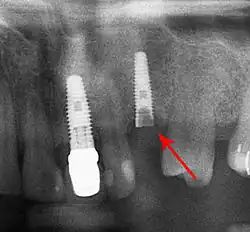

Beyond the possibility of mechanical failure[73] which may be due to poor prosthetic fitment, wear and tear, or user-induced actions such as bruxism, dental implants are also subject to peri-implant mucositis and peri-implantitis, where gum tissue and bone mass around the implant are resorbed, and the implant gradually becomes loose, and has to be removed.[74][75] In addition, although titanium is generally well tolerated by the body, there have been cases where the build-up of titanium particles released by the implant may cause systemic inflammatory response.[76] Because there is no dental enamel on an implant, it does not fail due to cavities like natural teeth. While large-scale, long-term studies are scarce, several systematic reviews estimate the long-term (five to ten years) survival of dental implants at 93–98 percent depending on their clinical use.[2][3][4] During initial development of implant retained teeth, all crowns were attached to the teeth with screws, but more recent advancements have allowed placement of crowns on the abutments with dental cement (akin to placing a crown on a tooth). This has created the potential for cement, that escapes from under the crown during cementation to get caught in the gingiva and create a peri-implantitis (see picture below). While the complication can occur, there does not appear to be any additional peri-implantitis in cement-retained crowns compared to screw-retained crowns overall.[77] In compound implants (two stage implants), between the actual implant and the superstructure (abutment) are gaps and cavities into which bacteria can penetrate from the oral cavity. Later these bacteria will return into the adjacent tissue and can cause periimplantitis.